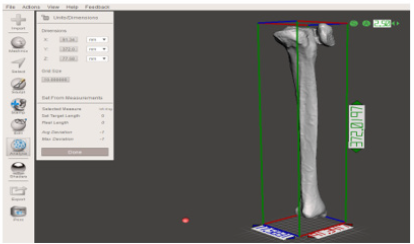

Because of the dimension of this particular bone (X = 91.34 mm, Y = 372 mm and Z = 77.58 mm) (Figure 16), MeshMixer is used to separate the geometry in two parts and generate a connection pin (Figure 17). The 3D printer used for this application is an FDM (Fused Deposition Modeling) technology, EZT3D Delta (Figure 18). In (Table 5) a material cost analysis was carried out based on the current price on market of the specific material per kg. Moreover, the autoclavability was considered despite the cost because of the particular medical application. Finally, the methodology studied, allowed to obtain a three-dimensional bone model in PLA that perfectly fits the anatomical structure of the CT images (Figure 19).